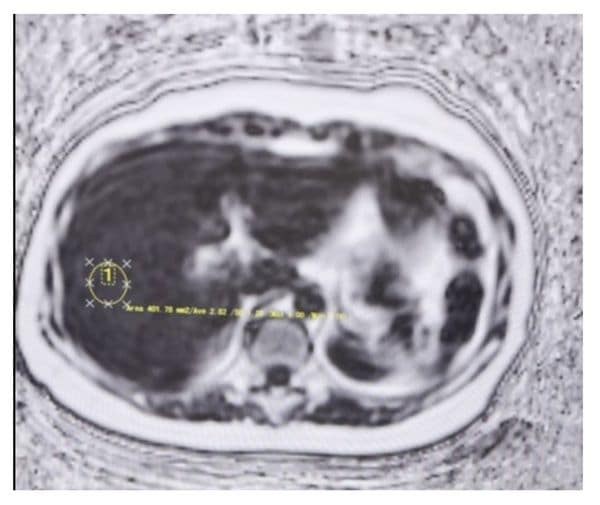

次に、脂肪定量画像(PDFF)で肝脂肪の量を見ましょう。

今城 画像上の任意の場所を選択すると、脂肪のパーセンテージが表示されます。いろいろな場所を測ることができるので、いくつか見てみると2.82、2.4、3.76%……というぐあいに出てきますね。5%以下が正常値なので、脂肪肝ではないと言えます。

丸く選択されたROI内の脂肪の%を見る